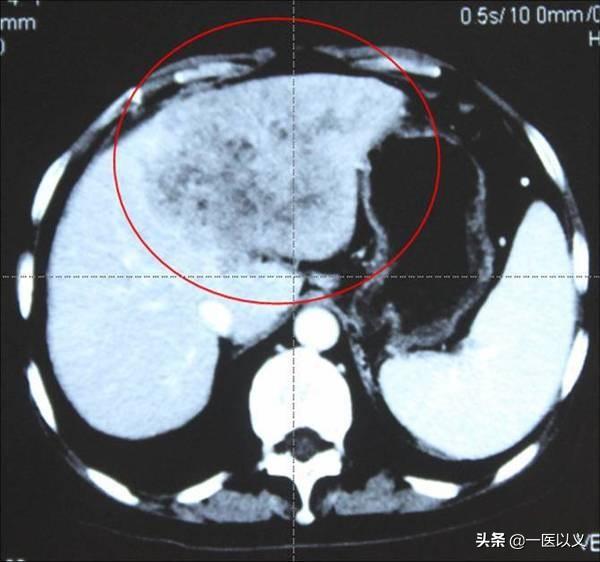

3番目だ。CT、MRIなどの肝臓の画像診断この検査ではさらに、肝臓の形状や、過去の肝臓の損傷を調べることができるため、CTで異常があっても現在の損傷を反映していない可能性がある!

- しかし、肝CTにも利点がある。何といっても、肝臓の完全な構造と病変を示すことができ、これは肝臓超音波検査とは比較にならない。肝臓の腫瘍を例にとると、肝臓のCTは病変の位置、大きさ、形態を明瞭に示すことができ、病気の診断と治療のある程度の指針となる。また、肝腫瘍性疾患の鑑別診断においても、肝高度CTの価値は高く、肝癌、肝血管腫、肝嚢胞などを鑑別することができる。

プライマリ・ケア病院では、フィルムの読影レベルや機器の条件から、磁気共鳴(MR)に比べて腹部CTが多く行われている。肝臓の場合、プレーンCT(造影剤なし)では肝嚢胞、肝膿瘍、肝内結石などを見ることしかできません。肝腫瘤の性質をさらに詳しく調べるには、強調CTが必要です。強調CTとは何ですか、なぜ必要なのですか?造影CTとは、腕の血管から造影剤を注入し、造影剤が動脈や静脈を通って肝臓に到達し、画像を現像する検査です。スキャンされたフィルムはプレーンフィルムと比較され、ほとんどの場合、肝臓の腫瘤の性質がわかります。

強化CTはもっと高価ですが、それでも肝腫瘤の性質が100%確実ではありません。ある検査を以下に続けます。